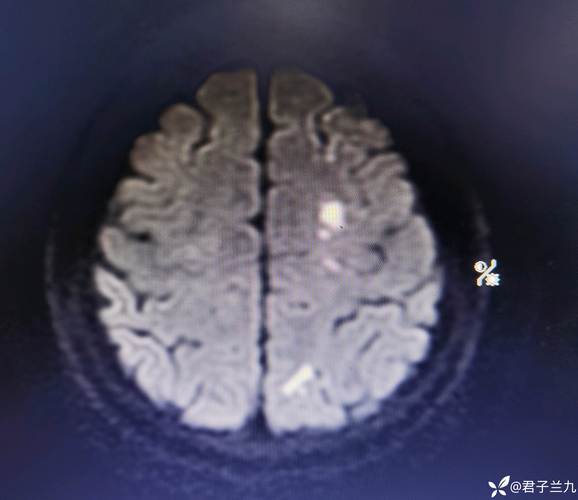

脑内多发缺血及腔梗灶

(图片来源网络,侵删)

• 就像水管里长了水垢,大脑的动脉血管壁内也会脂质沉积,形成斑块。

• 这些斑块会使血管管腔变窄,导致血流不畅,引发缺血。

• 斑块脱落形成的微小栓子也可能堵塞远端的小血管。